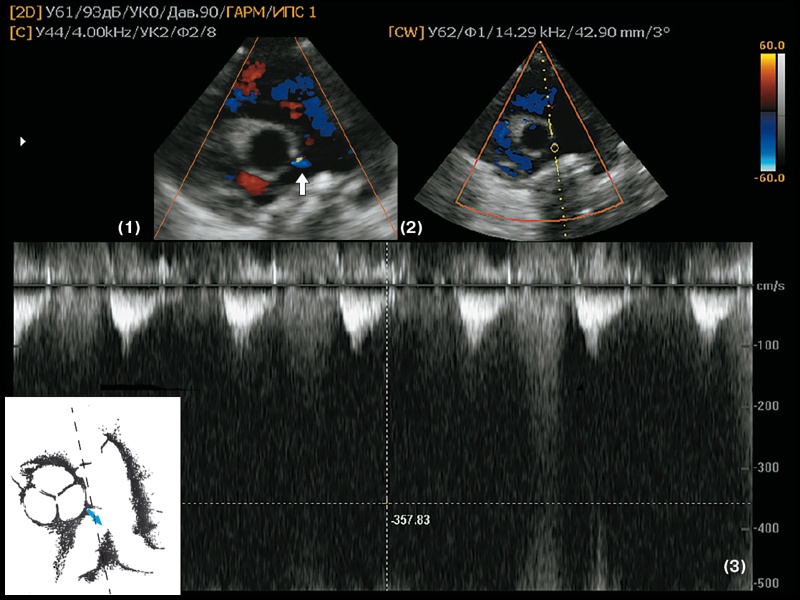

Наибольшие скорости в проекции КФ регистрируются при их выявлении в проксимальных отделах КА, ближе к устью ЛКА и ПКА. В этих случаях характеристики регистрируемых потоков оказываются схожими с таковыми в проекции парапротезных фистул и лево-правых шунтов, когда скорости потоков достигают 4–5 м/с (рис. 4, 6).

б) Апикальный доступ, четырехкамерная позиция. В режиме CW регистрируется высокоскоростной диастолический поток, Vmax до 4,58 м/с, Gmax – 84 мм рт.ст. Учитывая высокие скорость и градиент давления, а также фазу сердечного цикла, в которую регистрируется поток, в качестве единственной возможной причины его появления рассматривается только коронарная фистула между проксимальным сегментом коронарной артерии (наиболее вероятно, огибающая артерия левой коронарной артерии) и полостью левого желудочка.